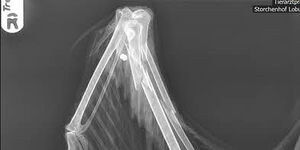

Als im August letzten Jahres der Anruf aus dem kleinen Dorf Dabrun in der Nähe der Lutherstadt 'Wittenberg kam, ich habe hier einen Storch, der nicht mehr fliegen kann, war es eine Meldung wie so viele im Jahr. Eine erste Untersuchung in Wittenberg ergab jedoch, dass auf diesen Storch geschossen wurde. Der Knochen des rechten Flügels war gesplittert und die Diabolo steckten sogar noch.

Der Bruch wurde versorgt, sogar genagelt. Dr.Mensing leistete erneut wieder eine hervorragende Arbeit in seiner Tierarztpraxis in Magdeburg. Erst danach konnten die Geschosse entfernt werden. Luther, wie er aufgrund seiner Herkunft nun genannt wurde, war kein einfacher Patient, aber immer recht munter. Die Wunden heilten.